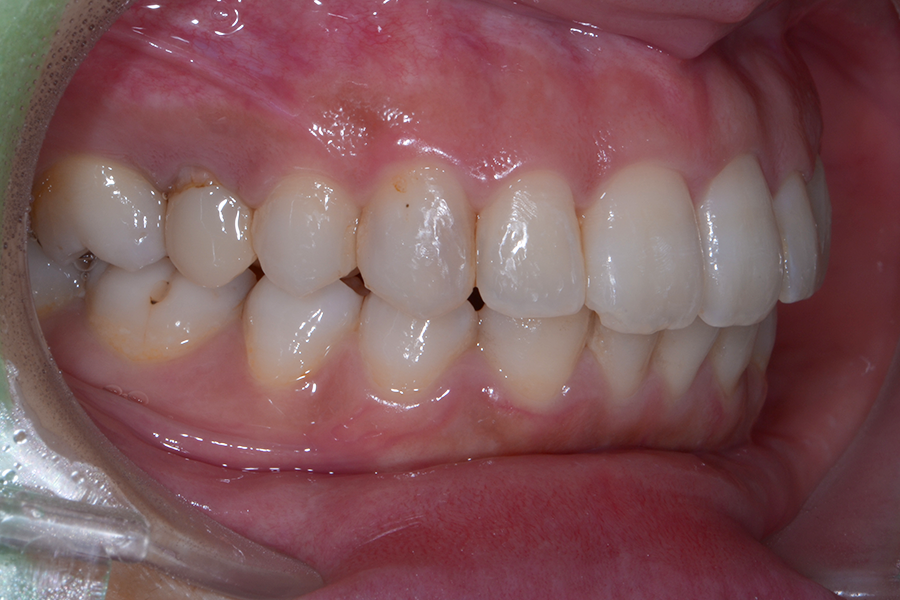

• 治療後